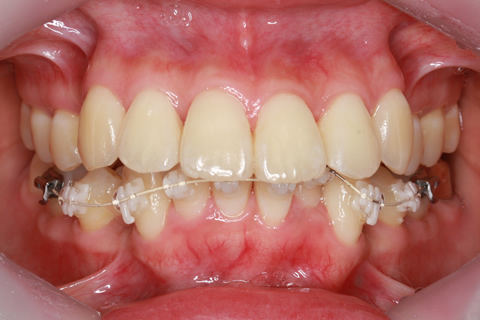

症例

治療前

治療中

治療後

- 年齢・性別

- 30歳女性

- 治療期間

- 3年0ヶ月

- 抜歯

- 上下左右4番抜歯

- 治療費

- 110万円

- 備考

- マルチブラケットを用いた矯正治療

- 治療内容

- 上下顎前突を4本抜歯にて矯正治療

- 施術の副作用(リスク)

- 表側矯正と比較して、歯根の角度を確立する「トルク」の力がかかりにくい。